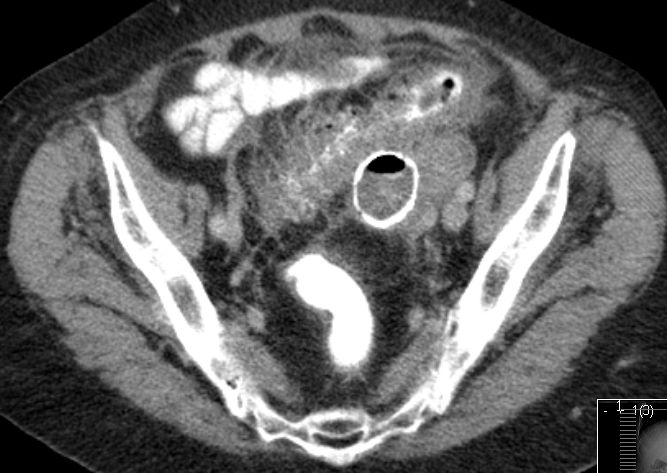

Konglomerattumor im linken Unterbauch: abszedierende Divertilulitis und Peridivertikulitis

mit angrenzenden pseudozystisch demarkierten Fettgewebsnekrosen und mit metaplastischer Verknöcherung der Pseudozystenwand.